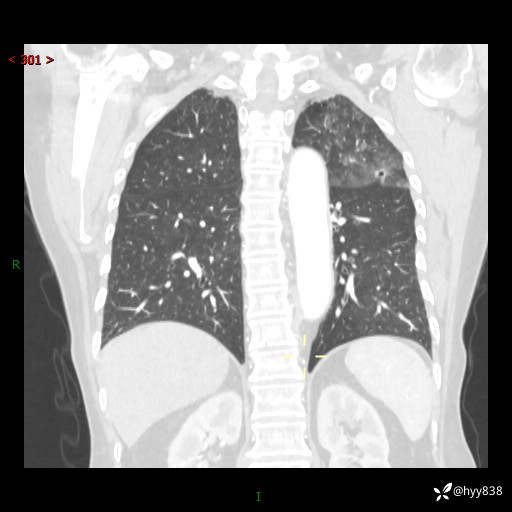

老年女性,偶然发现肺结节10天。结节不大,空洞不小,还牵拉胸膜---结果公布~

胸部CT增强(2024.8.2)